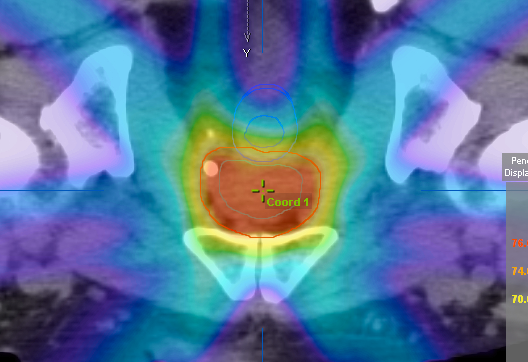

α)外照射療法:強度変調放射線治療(IMRT)

IMRT(intensity modulated radiotherapy)は患者さん毎に個別にコンピューターで治療計画と立て、より高エネルギーX線の強さを細かく制御することで腫瘍部分のみに放射線を集中させ,周囲正常組織への照射を軽減させる画期的な方法です。IMRTにより通常の放射線治療より多くの放射線を前立腺のみに照射することができ、周囲組織である直腸や膀胱への照射量を減らすことができるので効果が高まり、副作用が軽減できます。精密な線量計算、治療精度の確保が必須となるために、一部の施設でのみ行うことができる治療法です。当院では放射線治療科と連携し、IMRTで治療を行っています。

月曜日から金曜日まで週5日間治療し、約2ヶ月かかります。照射線量は74-78グレイです。1回の治療時間は10分〜15分程度で、外来通院で治療が出来ます。合併症は膀胱刺激症状(頻尿、排尿困難)、放射線性直腸炎(頻便、残便感、出血)、直腸潰瘍、尿失禁、性機能障害などがあります。